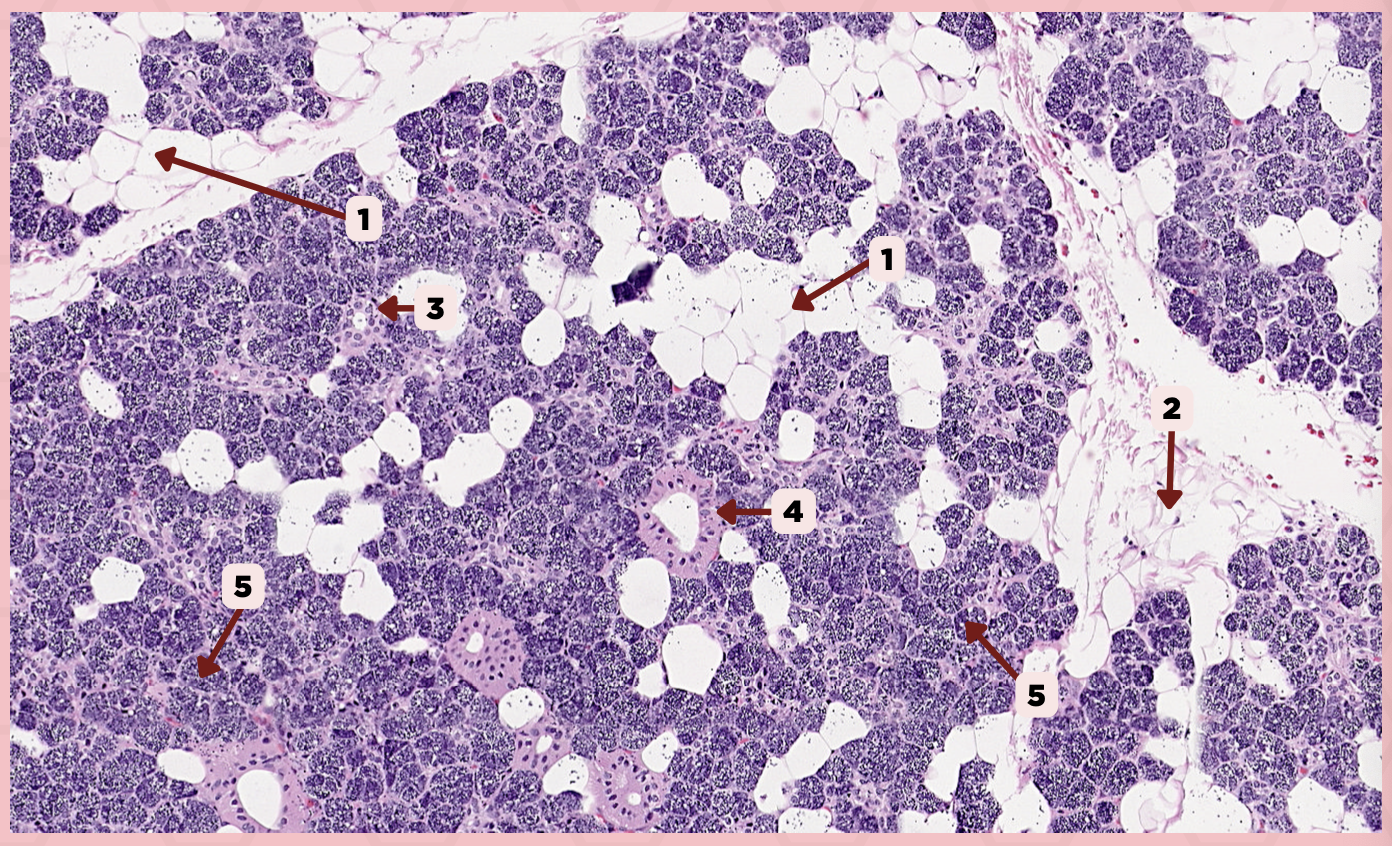

Parotid

Identify the specimen.

Vein

Identify the structure labeled as 1.

Artery

Identify the structure labeled as 2.

Nerve

Identify the structure labeled as 3.

Interlobular Septa

Identify the structure labeled as 4.

Interlobular Duct

Identify the structure labeled as 5.